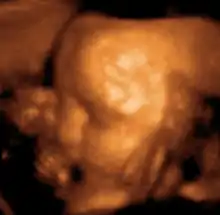

| 12 weeks | Uterus is the size of a grapefruit | Head grows faster than the rest of the body; facial features are apparent, but there is no layer of fat yet and the skin is translucent; gender can be distinguished via ultrasound; fingernails appear |

- By 20 weeks the fetus will be about 6 1/3" long and weighs 12 oz. Movements are for more coordinated. The sexual organs are well developed and are usually visible on ultra sound.